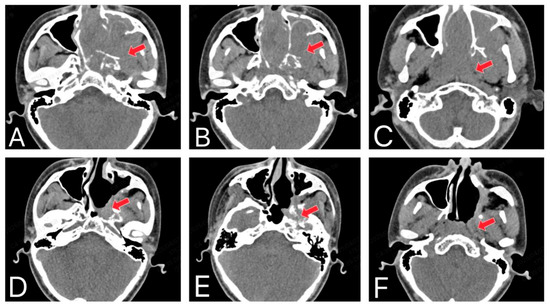

Figure 2.

The invasive nature and recurrence of JNA. (A–C) CT shows that the original JNA originates from the posterolateral wall of the nasal cavity, near the pterygopalatine fossa region, and invades the surrounding bone. (D–F) The CT shows a recurrent JNA after surgery (The red arrow in the image indicates the lesion site).